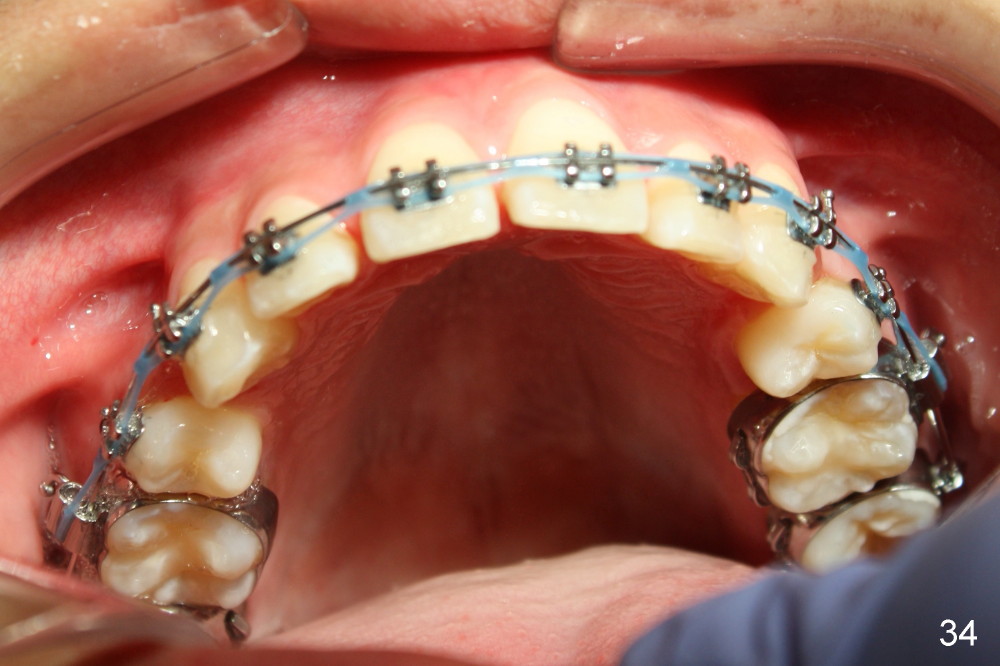

Prior to bracketing, the mesiodistal space for #18 is planned to be obtained by moving #20 and then #19 mesially (Fig.31-35, 16x16 ss). The six anterior lower teeth are tied together in a figure 8 fashion. Power chains are placed between the lower canine and the 2nd bicuspids. The upper diastemata are to be closed by power chains between the 1st molars.